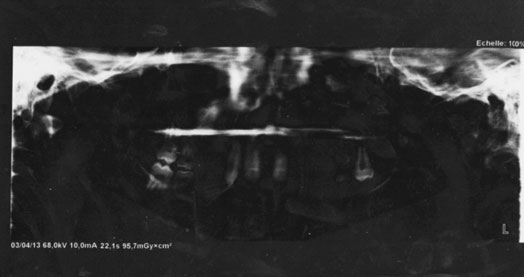

L’examen radiologique révèle, au niveau mandibulaire, l’absence d’os alvéolaire confirmant l’agénésie. Ce résultat va dans le sens de l’examen clinique qui a révélé une crête fine et résorbée rappelant celle du nourrisson. Par ailleurs, l’examen montre une absence des germes des dents permanentes au niveau maxillaire et mandibulaire (Fig. 4). Ces deux éléments confirment l’agénésie des dents permanentes.